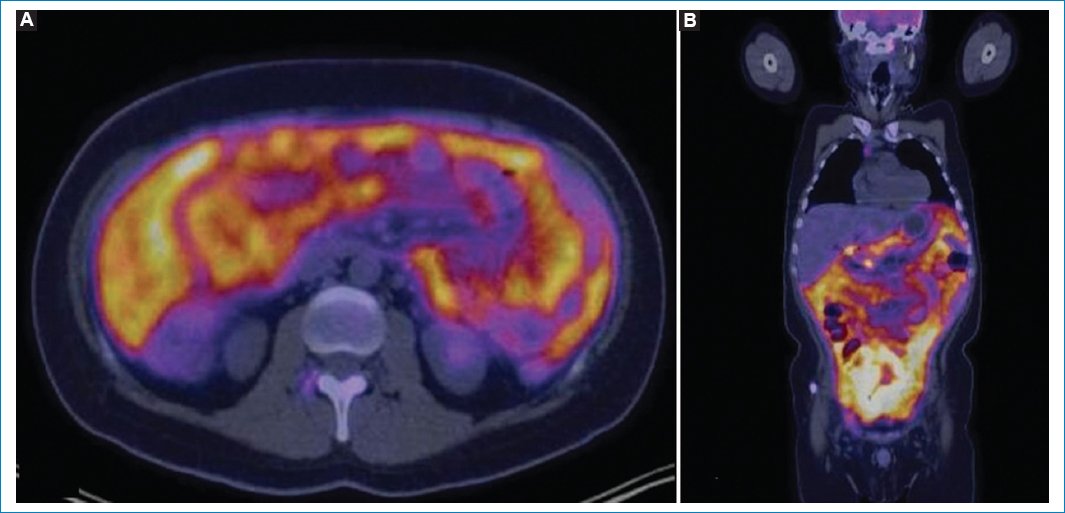

Algunos autores, como Benameur et al.34 y Roy et al.35, han introducido un concepto nuevo respecto a la LP, el “superescáner peritoneal”, para referirse a los casos de hipermetabolismo difuso y excesivo de la 18F-FDG por el peritoneo, con el consiguiente menor consumo glucídico por el resto del cuerpo, en particular del cerebro, el corazón y los riñones (Fig. 16). Este concepto se denomina así por su similitud con el del “superescáner óseo” en el estudio centellográfico para el compromiso difuso del hueso34.

Figura 16. Imágenes axial (A) y coronal (B) de fusión PET-TC en un caso de “superescáner peritoneal”, con excesivo consumo de 18F-FDG por el peritoneo y el consecuente menor metabolismo del encéfalo, el corazón y los riñones.